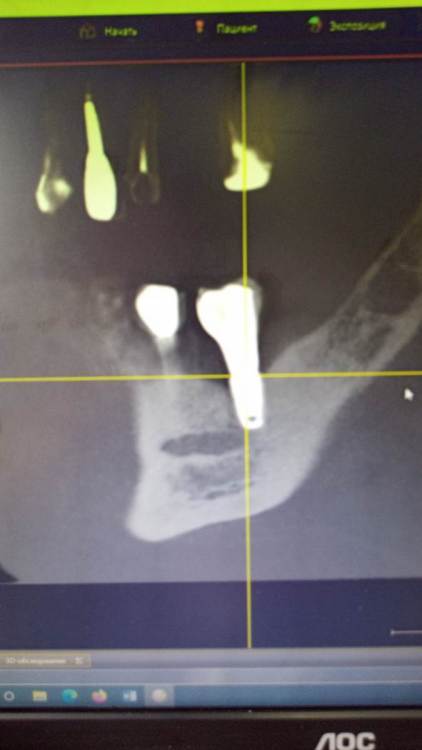

Зндрю Опубликовано 2 февраля, 2024 Автор Поделиться Опубликовано 2 февраля, 2024 (изменено) КТ имеется . Окончание импланта лежит на нижней ветви тройничного нерва, но не травмирует его. Со слов независимого имплантолога, у которого был на консультации, иначе симптомы были бы неврологические , а их нет . Изменено 2 февраля, 2024 пользователем Зндрю Ссылка на комментарий

kramer Опубликовано 7 февраля, 2024 Поделиться Опубликовано 7 февраля, 2024 В принципе понятно. Лично мое мнение, что надо удалять оба имплантата (ближний выглядит недозаглубоенным (плохо видно), дальний слишком близко к нерву, что скорее всего и дает симптомы. Установить новые импланты, сделать мостовидную конструкцию. Ссылка на комментарий

Зндрю Опубликовано 7 февраля, 2024 Автор Поделиться Опубликовано 7 февраля, 2024 (изменено) 3 часа назад, kramer сказал: В принципе понятно. Лично мое мнение, что надо удалять оба имплантата (ближний выглядит недозаглубоенным (плохо видно), дальний слишком близко к нерву, что скорее всего и дает симптомы. Установить новые импланты, сделать мостовидную конструкцию. На месте дальнего годом раньше стоял аналогичный имплант, но он был расположен выше. Период интеграции с костью сроком в 4 месяца он пережил успешно, а вот после установки формирователя десны началось воспаление, сопровождаемое обильной грануляцией десны, которое закончилось периимплантитом и удалением данного импланта . Через полгода на это же место был установлен нынешний имплант, но уже с максимальным погружением в кость. При его установке врач попал мне им в тройниный нерв, это было ясно потому как меня словно током ударило. Он тут же открутил его немного обратно и спросил меня, чувствую ли я боль, на что я ответил что нет . Он так и оставил, и дальнейший период интеграции с костью проходил без осложнений. Установка формирователя десны тоже осложнений не вызвала , боли начались только после установки коронки. Самое главное - что первый винт стоял на достаточном расстоянии от нижней ветви тройничного нерва, но болевые ощущения была абсолютно идентичны что и со вторым винтом - а именно появлялись исключительно через несколько часов после вкручивания коронки, при этом я даже еще ни разу не успевал ничего жевать . Изменено 7 февраля, 2024 пользователем Зндрю Ссылка на комментарий